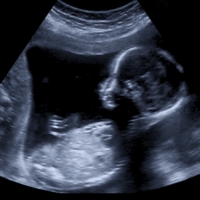

4. Describe the life cycles of a mammal, bird and reptile

Describe the life cycles of a mammal, bird and reptile